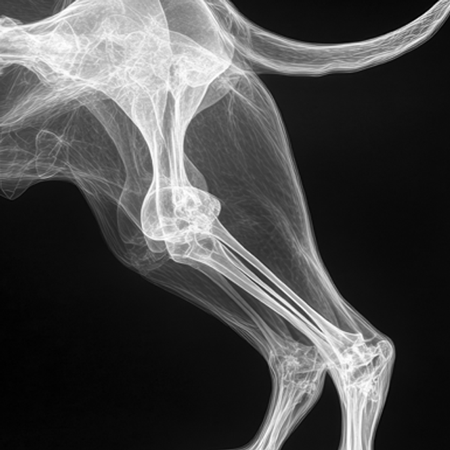

국내 최고 수준의 장비

Digital X-ray, 고해상도 초음파 등

진단 장비 갖추고 있으며

임상 경험이 풍부한 의료진이

직접 확인하고 치료 방향을 결정합니다.